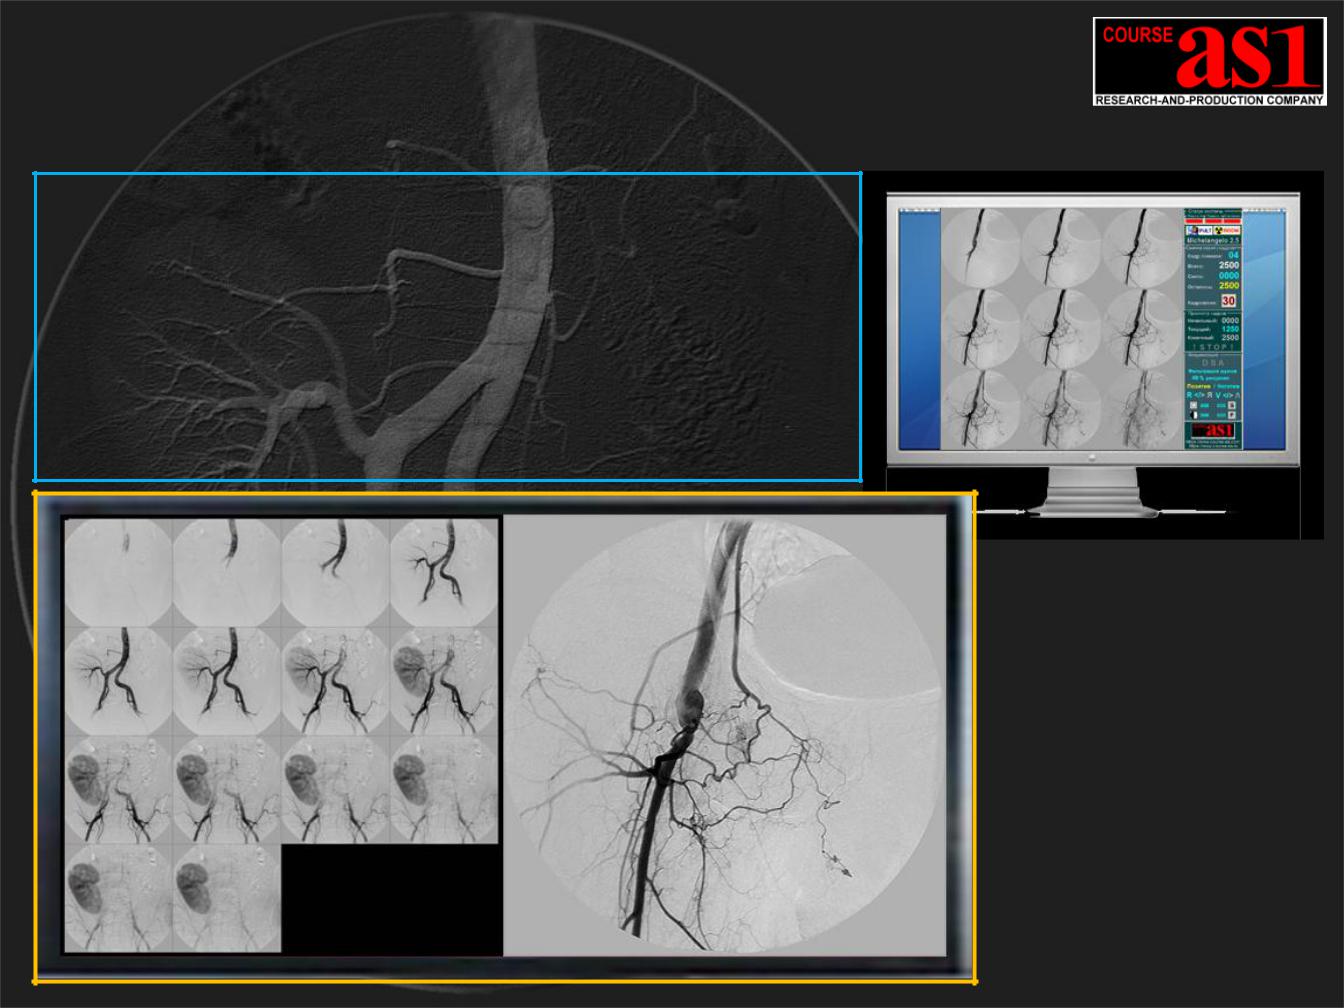

(представлена на изображении в левом нижнем углу)

Динамическая Визуализация обработанных X-ray изображений

Визуализация Реального Времени потока изображений сверх высокого разрешения параллельно в разных форматах на мониторы с разным разрешением.

Плавное масштабирование при визуализации с возможностью динамического отображения выделенного участка кадра:

1460 x 1460 ( 2 Mpix ) Zoom = 0.7 -:- 2

2092 x 2092 ( 4 Mpix ) Zoom = 0.5 -:- 3

2980 x 2980 ( 8 Mpix ) Zoom = 0.3 -:- 4

27” DICOM View monitor ( сверху )

15Mpix (5120 x 2880) or

30” DICOM Diagnostic monitor

6Mpix (3280 x 2048)

36” DICOM Diagnostic monitor ( слева )

8 MegaPixel

(4096 x 2160 x 10b)